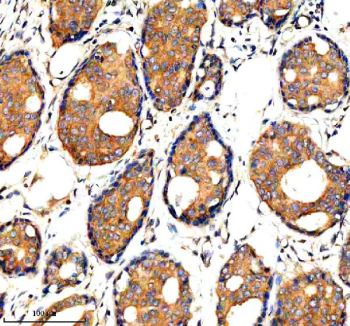

Immunohistochemical staining of ADAMTS1 using anti-ADAMTS1 antibody. ADAMTS1 was detected in a paraffin-embedded section of human breast cancer tissue. Heat mediated antigen retrieval was performed in EDTA buffer (pH 8.0, epitope retrieval solution). The tissue section was blocked with 10% goat serum. The tissue section was then incubated with 2 ug/ml rabbit anti-ADAMTS1 antibody overnight at 4oC. Peroxidase Conjugated Goat Anti-rabbit IgG was used as secondary antibody and incubated for 30 minutes at 37oC. The tissue section was developed using an HRP secondary and DAB substrate.